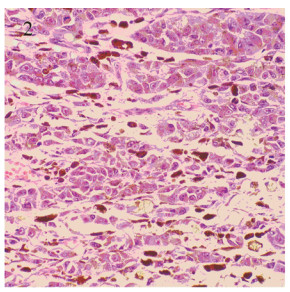

患者,男,63岁,因进食梗咽不适3月就诊。2018年6月22日胃镜病理检查:(食管距门齿37~45 cm)组织表面被覆复层鳞状上皮,间质内见梭形细胞弥漫分布,细胞异型明显,核分裂相罕见,考虑为间叶源性梭形细胞肿瘤。免疫组织化学:CK(-),CK7(-),CK20(-),p40(-),p63(-),Vimentin(+),CD34(-),Ki67 50%(+)。2018年7月9日上腹部CT示食管下段贲门、胃底占位,周围淋巴结肿大。2018年7月17日全麻下行食管下端及胃底肿物切除术,术中探查食管下段及胃底分别扪及肿瘤各约3、4 cm直径大小,周围淋巴结肿大。术后病理:(下段食道及近端胃切除根治标本)恶性黑色素瘤(图 1~2),见肿瘤两枚,位于食管下端近贲门处,大小分别为4.5 cm×3.8 cm×3.0 cm及5.0 cm×3.5 cm×2.8 cm,两者相距约3.0 cm;另送“食管贲门切缘”和“胃底切缘”未见肿瘤累及;淋巴结情况:贲门旁组2/4,小弯侧0/8,大弯侧0/5有转移;大网膜未见肿瘤累及;免疫组织化学: CK(-), CK7(-),CK20(-),CEA(-),Villin(-),p40(-),CK5/6(-),Vimentin(+), A103(+),S-100(+),HMB45(-),CK8/18(-),p53(+),Ki67 50%(+);BRAF、C-KIT基因检测未见突变。患者2013年因“左肾透明细胞癌”行左肾切除术,无高血压及糖尿病病史,否认肿瘤家族史。